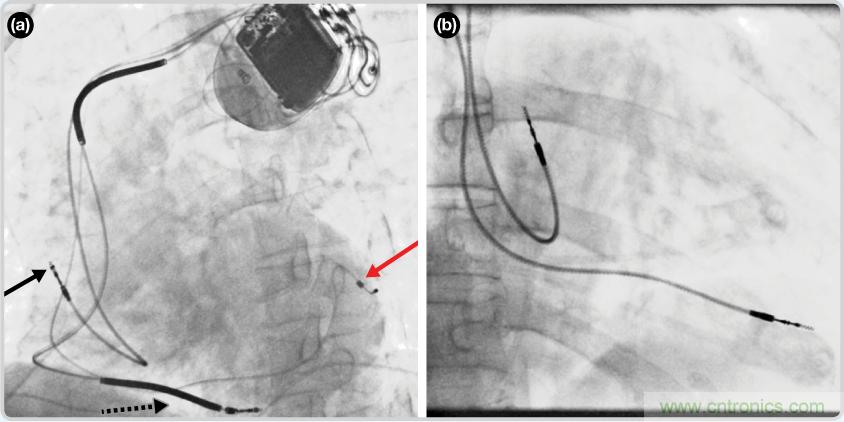

CRT器件在圖4(a)中的透視圖像中可以看見。醫師就是利用這種影像來放置導聯線的。對于非專業人士來說,這種影像是很難解讀的。可以看到心臟淡淡的輪廓——這是搏動中的心臟的靜態視圖。起搏器位于右心房上,心臟頂點指向右下方。在這個典型的導聯線放置實例中,黑色箭頭指向右心房導聯線。虛線黑色箭頭指向右心室導聯線。紅色箭頭標示的導聯線只能看到一部分,這是左心室導聯線(紅箭頭指向電極尖端)。圖4(b)展示的是雙腔起搏器的典型導聯線放置透視圖像。右心房導聯線指向上方,置于右心房中。右心室導聯線則位于右心室頂部。

圖4. 起搏器導聯線放置的透視圖像3 (a). 單腔起搏器;(b).雙腔起搏器